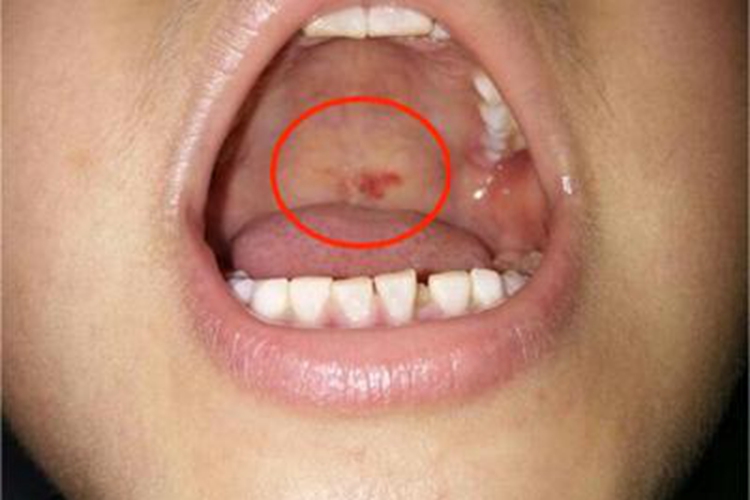

获得性风疹前驱期症状轻微,仅表现为低热、全身不适、纳差及咳嗽、咽痛等,可累及软腭,黏膜表面可出现细小的血点,为玫瑰色或出血性,能融合成红斑。